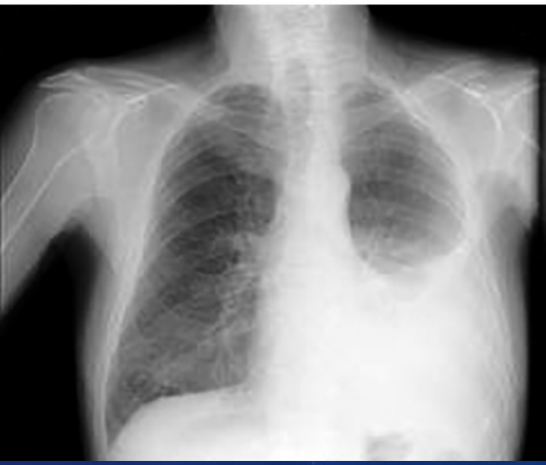

Síndrome Torácica Aguda

A + Letal em crianças maiores

• Causa principal: Infecções, sec: Tromboembolismo, hemácias falcizadas pulmonares e edema pulmonar

• QC: Dor torácica aguda, tosse, taquidispneia, sibilância, estertores e febre PODE estar + -Crise álgica

• Exames: Rx tórax, hemograma, hemocultura e PCR

• TT: Hospitalização, antibioticoterapia ampla, oxigênio e manter conc de Hb >10g:dl